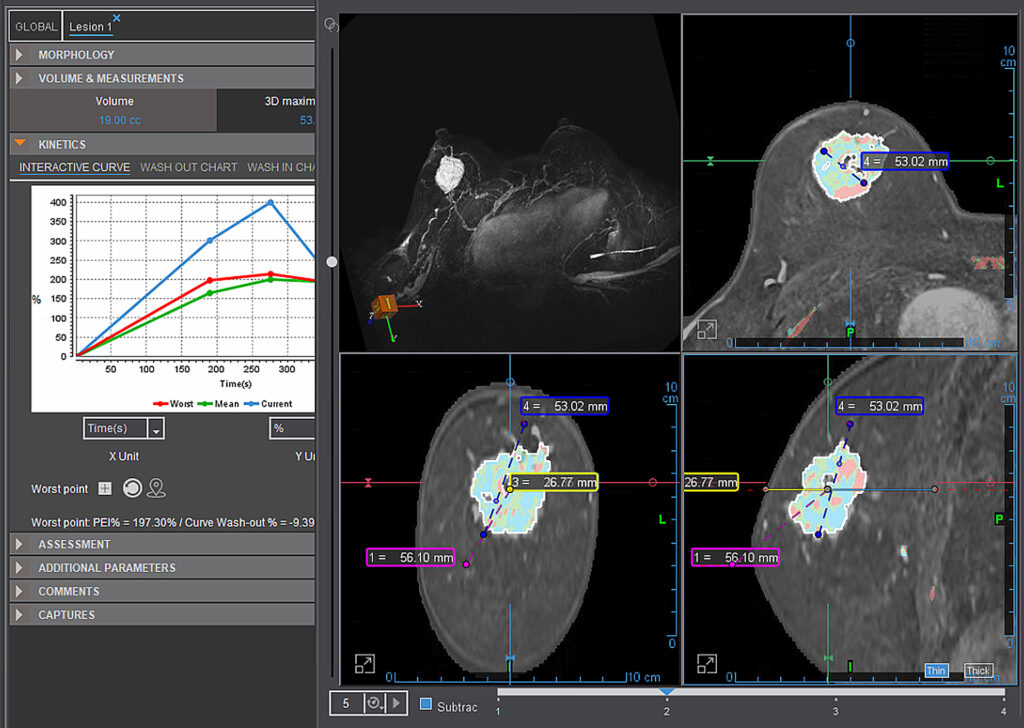

MR Breast (Basic)

Olea MR Breast applications are efficient tools for breast lesion detection, characterization and staging. Olea MR Breast applications are efficient tools for breast lesion detection, characterization and staging.

MR Breast Advanced (breastscape®)

This is a semi-automated solution for diagnostic assistance in breast lesions. Automatically computes parametric maps, segmentation of lesions and calculation of distances, lesion evolution follow-up, preparation of BI-RADS® Atlas.